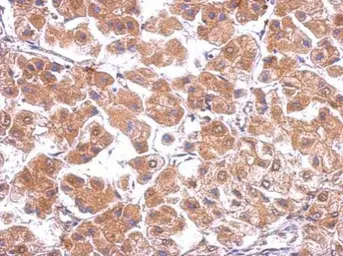

Anti-Cav beta 4 antibody [C3], C-term used in IHC (Paraffin sections) (IHC-P). GTX100202

GTX100202 IHC-P Image

Immunohistochemical analysis of paraffin-embedded human hepatoma, using CACNB4(GTX100202) antibody at 1:500 dilution.

Antigen Retrieval: Trilogy™ (EDTA based, pH 8.0) buffer, 15min